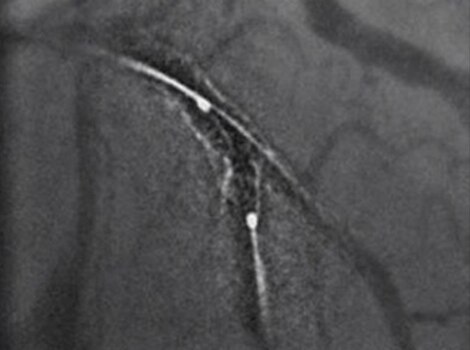

Intervention

For patients sent for revascularization in the catheterization lab, attempts are made to rapidly access the culprit artery and complete further assessment of coronary tree. Rapid intervention can help minimize time to reperfusion from first medical contact.

Innova IGS 5 or Discovery IGS 7

Helps reduce use of contrast and dose with one of the industry’s highest ratings for Detective Quantum Efficiency (DQE).12 Read More

PCI ASSIST13

Help plan, assess and guide interventional procedures with improved visibility up to 85 percent in moving anatomy. Read More

Successful PCI of the stenotic lesions involves planning, guidance, and assessment of the culprit lesion and assessment of the remainder of the coronary tree.

Innova IGS 55

Helps reduce use of contrast and dose with one of the industry’s highest ratings for Detective Quantum Efficiency (DQE).

PCI ASSIST6

Help plan, assess and guide interventional procedures with improved visibility up to 85 percent in moving anatomy.